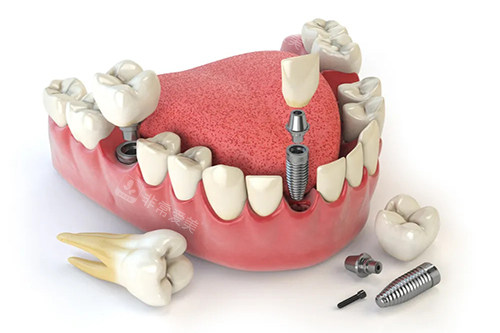

多颗牙齿种植ct

牙齿种植牙模型卡通示意图

牙齿种植卡通示意图